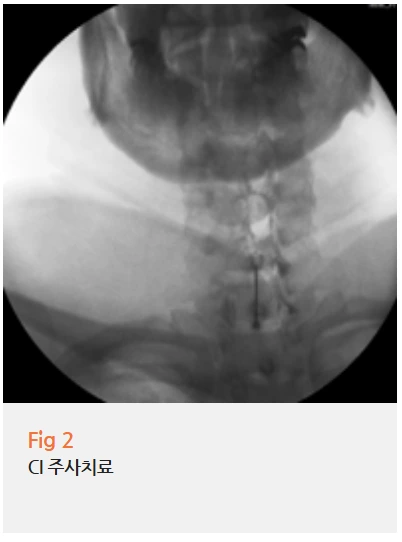

진단이 명확해지니 치료 방향도 선명해졌습니다.

문제가 되는 경추 신경근을 정확히 타겟팅하는

CI(C-arm Intervention) 주사치료를 계획했어요.

CI 주사치료는 C-arm이라는

영상 장비를 실시간으로 보면서 진행하는 시술이에요.

맨눈으로 대충 놓는 주사가 아니라,

문제가 되는 신경 부위를 정확히 보면서 약물을 주입하는 거죠.

왜 이렇게 정밀하게 해야 하냐고요?

목 주변은 중요한 신경과 혈관들이 밀집된 부위예요.

1mm의 차이로도 치료 효과가 완전히 달라질 수 있거든요.

그래서 통증의학과 전문의의 숙련된 기술이 필요한 시술입니다.